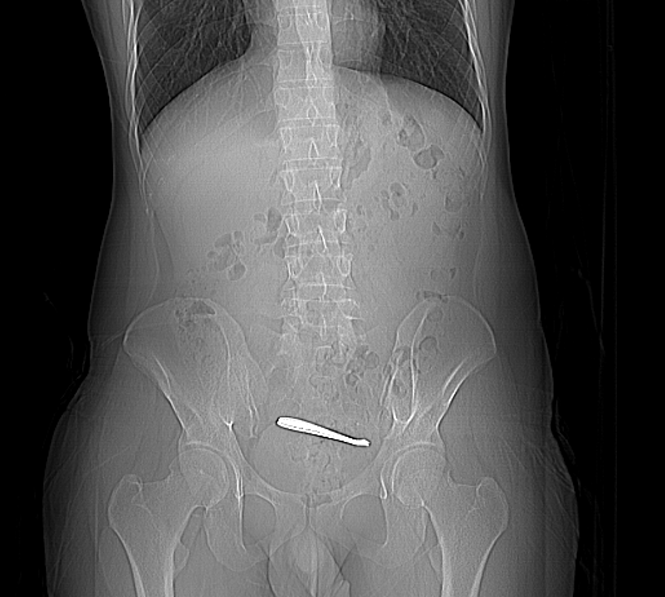

据悉,在邻近春节前的两天,28岁的张先生(化名)因腹痛一周在西安就诊,查腹部CT显示肠道内有一长条形高密度影。原来,在此之前3周,张先生曾误吞入勺子,现勺子卡在肠道中无法排出,导致了腹痛,就诊的医生告知患者要行外科手术才能将其取出。因要外科手术让张先生犯了难,此时,张先生身边的朋友曾经因消化道异物来南京鼓楼医院就诊,成功取出了异物。

张先生随即乘飞机赶来南京,至鼓楼医院本部就诊。入院CT显示异物位于盆腔,消化科团队随即为张先生安排肠镜。